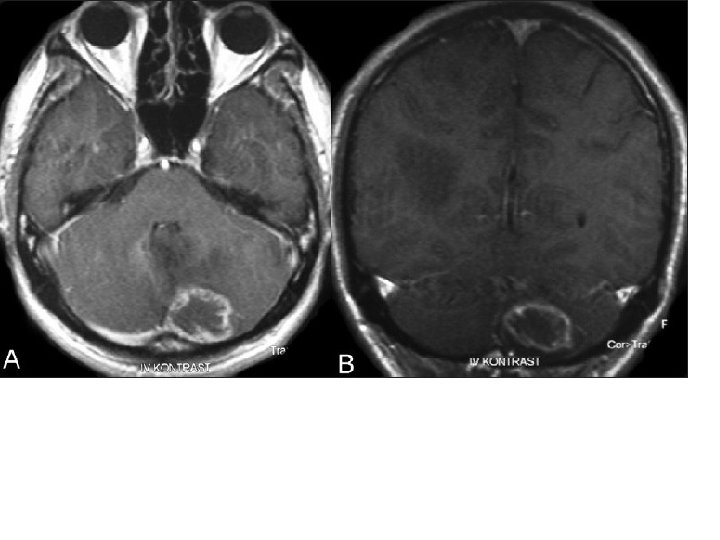

Diagnosis • large non enhancing vesicle that is well demarcated from the surrounding brain parenchyma. • Some lesions may be calcified. • epidural cysts have a biconvex shape or a multilocular appearance and may be associated with bone erosion.

Pathology • E. granulsus cysts are large, spherical, and well demarcated from surrounding tissue. • within the CNS, these cysts may be located in the brain parenchyma, ventricular system, subarachnoid space, epidural space, orbits, and both the epidural and subarachnoid spaces in the spinal canal.

Diagnosis • On neuroimaging studies, alveolar hydatid disease is characterizednby multiple lesions surrounded by edema, with ring-like enhancement mimicking other infectious or neoplastic diseases of the CNS. • CT is better than MRI for demonstrating lytic lesions in vertebral bodies. • Immunologic diagnosis is better with alveolar echinococcosis than with cystic hydatid disease.